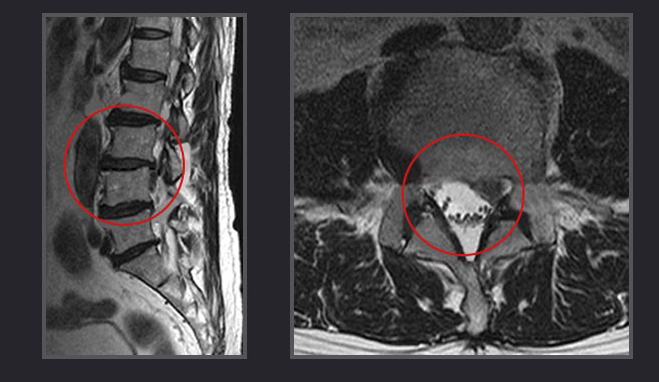

척추는 추골이라고 불리는 뼈가 연결되어 있습니다요추란 척추 아래쪽에 있으며 5개의 척추체로 구성된 부분입니다. 척추와 척추 사이에는 추간판이 있습니다. 추간판은 수분을 많이 포함한 젤리 형태의 수핵과 그것을 둘러싼 섬유륜이라고 불리는 연골조직의 이중구조로 되어 있어 요추에 가해지는 압력을 분산시켜 충격 완화 쿠션 같은 역할을 하고 있습니다.그러나 노화 등에 의해 수핵을 둘러싼 섬유륜이 탄력을 잃으면 작은 균열이 생겨 수핵의 일부가 밖으로 튀어 나옵니다. 이 밀려난 수핵이 신경을 압박하기 때문에 허리에 통증이 생기는 것입니다. 이 상태를 방치하고 있으면, 수핵이 점점 밀려 나오고, 통증이나 저림이 점점 강해져 갑니다.허리디스크는 고령보다 20대에서 40대에 이르는 상대적으로 젊은 남성에게 더 많은 질환입니다. 앞으로 구부리거나 엉거주춤한 자세를 장시간 계속하거나, 무거운 물건을 갑자기 들어 올렸을 때 등에 발병할 위험이 있습니다.

요추는 5개의 추체와 5개의 추간판으로 구성되어 있습니다. 그 중 디스크를 일으키기 쉬운 것은, 제4 요추와 제5 요추 사이에 있는 추간판과, 제5 요추와 천골 사이에 있는 요추입니다.

전자의 추간판탈출에서는 종아리 바깥쪽에서 엄지발가락에 걸쳐있고, 후자는 무릎 뒤쪽에서 발바닥을 걸쳐 통증이나 저림이 발생합니다.허리디스크의 경우 등을 펴고 있을 때나 자고 있을 때는 통증이 편해집니다. 반대로 등을 둥글게 하거나 구부리면 신경이 압박되어 통증과 저림 강해지는 것이 특징입니다.허리디스크로 병원에 내원하면 증상이 심하지 않다면, 약물치료와 물리치료와 운동치료를 병행합니다.그래도 증상이 좋아지지 않으면, 추간공 경막외 신경주사치료를 생각해 볼 수 있는데요.추간공 경막외 신경주사치료는 특수영상촬영장치인 C-arm을 통해서 병변부위를 실시간 확인하면서 진행하기에 정확도가 높고 염증이 생긴 신경뿌리가 있는 부위까지 주사바늘을 위치해서 약물을 투여하기에 일반적인 신경차단술보다는 통증개선에 효과가 좋습니다.